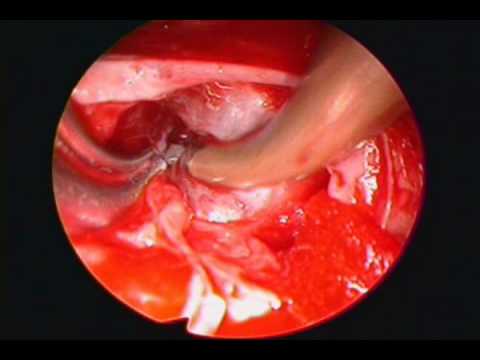

Dekompresja mikronaczyniowa - leczenie neuralgii...

Na filmie zaprezentowano mikronaczyniowe odbarczenie zastosowane w leczeniu neuralgii nerwu trójdzielnego. Zaprezentowany przypadek dotyczy pacjentki ze zdwojoną tętnicą móżdżkową górną. Jedna z tętnic...